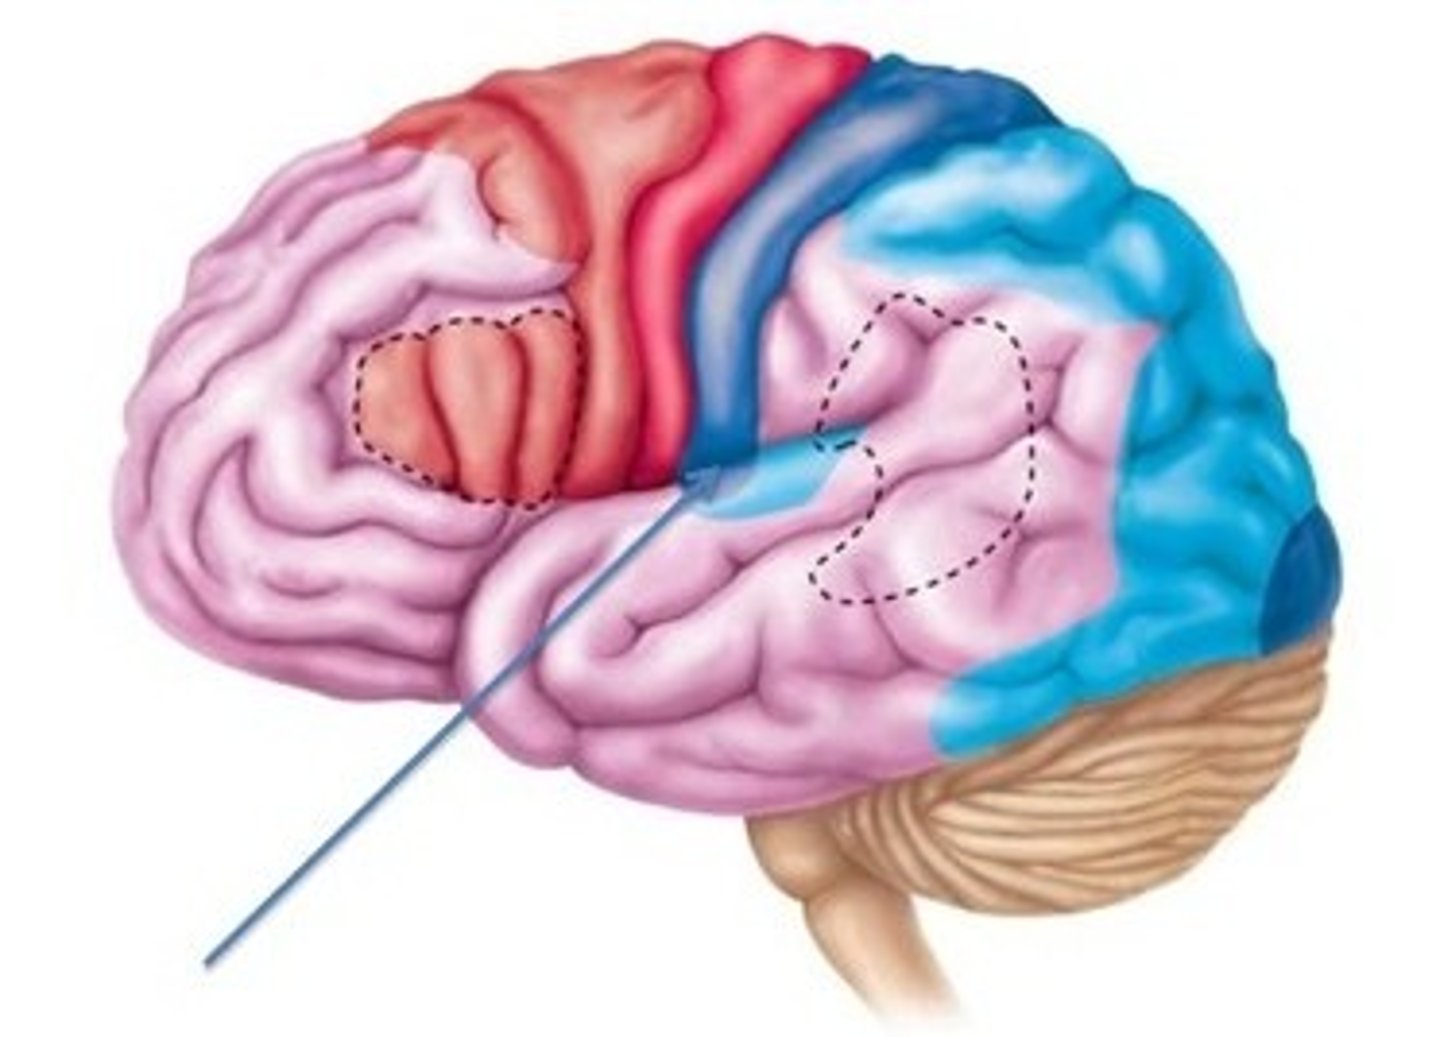

primary somatosensory cortex

•Located in postcentral gyrus of parietal lobes

•Receives somatic sensory information from

•Proprioceptors, touch, pressure, pain, temperature receptors

postcentral gyrus

the strip of parietal cortex, just behind the central sulcus, that receives somatosensory information from the entire body

sensory homunculus

Demonstrates that the area of the cortex dedicated to the sensations of various body parts is proportional to how sensitive that part of the body is